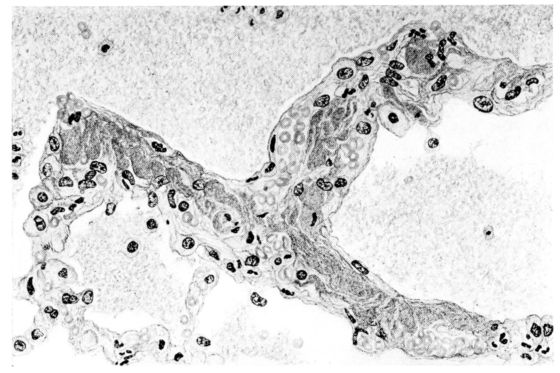

FIG. II. AUTOPSY NO. 98. DRAWING OF A SECTION THROUGH A TRACHEA SHOWING NECROTIZING HEMORRHAGIC INFLAMMATORY PROCESS OF THE MUCOSA.

The changes are less marked, perhaps, in the trachea than in its finer ramifications. The mucosa is constantly more or less destroyed and large areas, usually focal, are entirely devoid of their epithelial covering. This is replaced by a sparse exudate, composed largely of red blood cells, mucus, a small amount of fibrin, and nuclear fragments (Fig. II). It may dip into the submucosa for a short distance, but usually these indentures are associated with the ducts of the mucous glands into which the inflammatory reaction extends. A more striking feature than the exudate, however, is the edema and the congestion of the submucosa. The loose areolar tissue of the submucosa is spread widely apart, and throughout it distended blood vessels are very conspicuous. Occasionally such a vessel is broken and actual hemorrhage appears in the submucosa. Occasionally, too, the inflammation extends down the duct to the mucous gland itself, and here, also, aplastic inflammatory reaction is evident, inasmuch as the acini now stain intensely red with the cells undifferentiated from each other and specked here and there by broken remains of the dead nuclei (Fig. III). After the disease has continued for a short period, even at the end of five or six days, some regeneration of the epithelial lining may be seen (3) (Fig. IV). But despite this, the acute picture persists, and there goes on, side by side, an attempted repair characterized by epithelial regeneration and the same evidence of acute change. Since the lesion is essentially a superficial one, scars or contractures of any extent are not encountered in the trachea, even in examples of the disease that have ended fatally only after many weeks.[4]